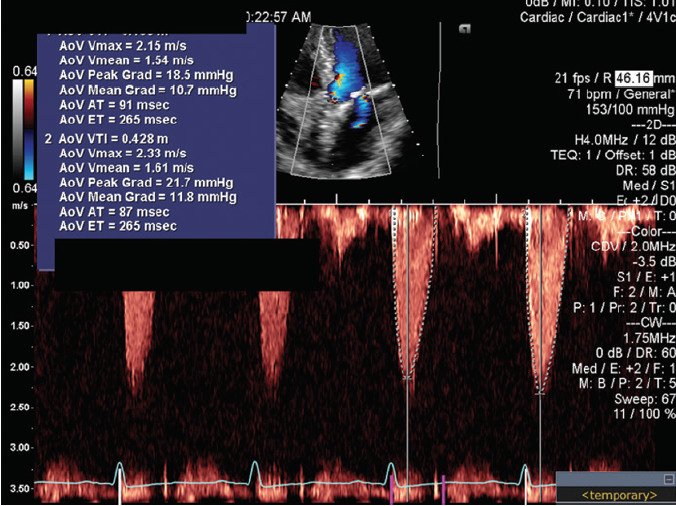

Figure 1. CTA of the chest, abdomen, and pelvis (A). Crosssection of the aortic annulus (B). Longitudinal section of the aortic root (C).

Based on the recently approved indication for transcatheter aortic valve replacement (TAVR) in intermediate-risk patients, as well as the patient’s preference after discussing the potential risks and benefits of both approaches, the heart team offered to proceed with TAVR. A chest/pelvis CTA demonstrated aortic annular sizing and peripheral anatomy suitable for a transfemoral (TF) TAVR; moderate calcification was noted in the left ventricle outflow tract (Figure 1). Coronary angiography demonstrated nonobstructive CAD.

TAVR was successfully performed with a 23-mm, balloon-expandable transcatheter heart valve (THV; Sapien 3, Edwards Lifesciences) via TF access, which provided 3.8% oversizing. The patient was extubated in the hybrid operating room immediately postprocedure with no complications. On postoperative day 1, TTE revealed a well-seated THV with a mean TVG of 17 mm Hg, an aortic velocity of 2.7 m/s, and no evidence of aortic insufficiency. The patient was discharged on postoperative day 2. The patient returned for follow-up 1 year after TAVR without cardiac symptoms or limitations (NYHA class I) and a sustained improvement in his functional capacity. At 1 year, TTE demonstrated a left ventricular ejection fraction of 75%, a mean TVG of 12 mm Hg, an aortic velocity of 2.3 m/s, and no evidence of aortic insufficiency (Figure 2).